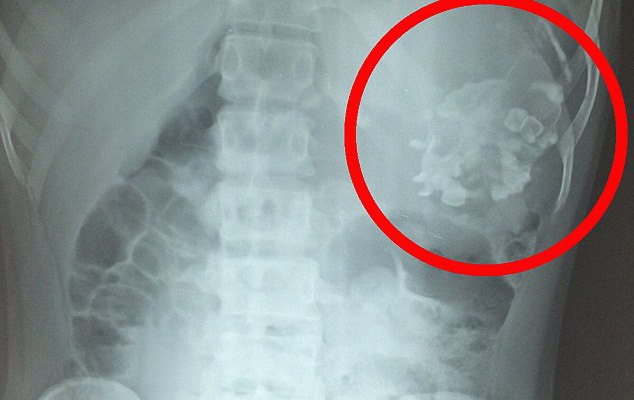

НЕПРИЈАТНО ИЗНЕНАДУВАЊЕ: Никој не би сакал да го има ова во стомакот!

Замислете го изненадувањето на докторите во Индија кога сфатиле дека причината за болка во стомакот на еден тинејџер бил деформиран фетус на неговиот брат близнак.Нерендра Кумар (18), бил одведен во […]